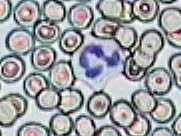

Imágenes tomadas de las preparaciones de los alumnos de 3º ESO sobre un frotis sanguíneo

Resolución:

181x136 píxeles